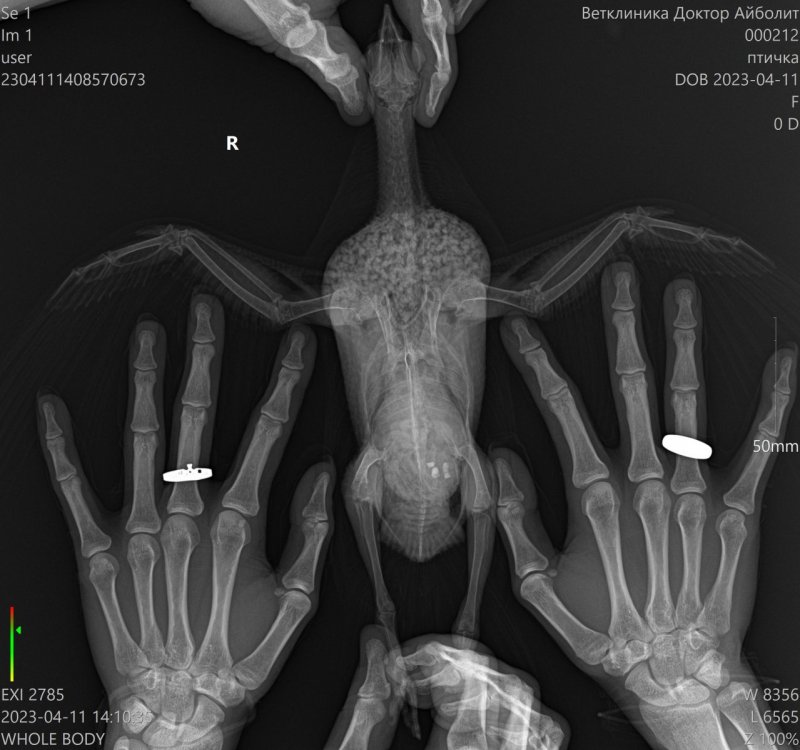

Людмила_М Опубликовано 24 апреля, 2023 Автор #39 Опубликовано 24 апреля, 2023 18.04.2023 в 22:16, маленький принц сказал: крыльями стоя на месте махи делает? Даю возможность пролететь через комнату раз 6 в день.. Да, это очень мало, видимо. Махи на месте - это как? Взять птицу в руки и дать возможность махать крыльями? Это его не испугает?) Второй визит к ветеринару оставил еще больше вопросов. С целой ногой все сложно, то ли на снимке плохо читается, то ли что, но врач предположил перелом одного пальца, хотя не реагируют на прикосновение все... Присутствует воспаление суставов ног. У меня уже появилась мысль, что он не ходит, потому что ему попросту больно. Печень на снимке вообще не просматривается. Поэтому диагноз - гепатомегалия. В добавок почечная патология, поскольку контур почек слишком четко очерчен, энтерит и кандидоз. Ну, и антибиотик ципрофлоксацин оказался неэффективным, то есть, 2,5 недели лечения псу под хвост. Хотя, это даже обнадеживает, поскольку объясняет отсутствие прогресса в состоянии птицы. В помете много непереваренной клетчатки. Все-таки, возможно, это частично связано с отсутствием гастролитов? Пишут же, что птице нужны камушки, не только песочек из минеральной смеси. Минералку, кстати, он по чуть-чуть, но клюет каждый день. Но там нет крупных фракций. Новое лечение включает амоксициллин, флуконазол, мезим для пищеварения, цистон для почек, гептрал и расторопшу для печени, глюконат кальция для костей - его мне уже здесь посоветовали. Насчет ног пока ничего... Надеюсь, что этот курс сработает.

Budgiek Опубликовано 24 апреля, 2023 #40 Опубликовано 24 апреля, 2023 @Людмила_М Вы не могли бы выложить снимки. Zosia возможно их посмотрит и напишет свое мнение.

Людмила_М Опубликовано 24 апреля, 2023 Автор #41 Опубликовано 24 апреля, 2023 15 минут назад, Budgiek сказал: Вы не могли бы выложить снимки. Zosia возможно их посмотрит и напишет свое мнение. Да, еще одно мнение врача по снимкам здесь не помешает, потому что для меня все так и осталось в тумане. 1

Budgiek Опубликовано 24 апреля, 2023 #42 Опубликовано 24 апреля, 2023 @Zosia Рентген. Вы не могли бы посмотреть, пожалуйста? 1